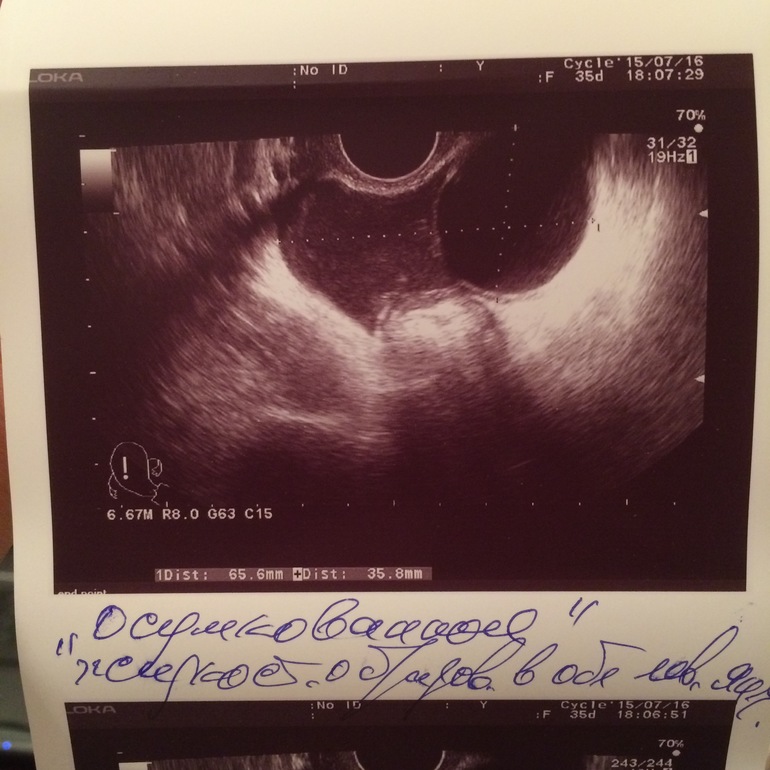

Сегодня была на узи, киста не рассосалась за 2 месяца и после гинекологического массажа размер 35мм,кто сталкивался и что делать? фото под кат

ой она вообще на протяжении 2 месяцев что я к нему на массаж ходила то увеличивалась то уменьшалась с 25 до 35, потом с 35 до 30 становилась сейчас 35мм,а с ней можно беременеть?

ну сейчас 8 д.ц и вроде как в левом яичнике там где и киста зреет Д.Ф уже 15мм